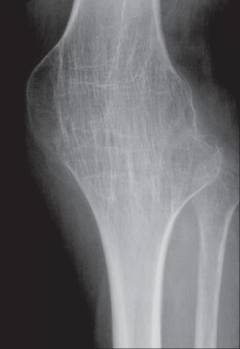

Особенности строения коленного сустава

Коленный сустав образован тремя костями:

- Мыщелки бедренной кости.

- Мыщелки большеберцовой кости.

- Надколенник.

Коленный сустав имеет форму блока. В нем возможны движения:

- сгибание на 135°;

- разгибание на 3°;

- вращение вокруг вертикальной оси примерно на 10°.

Особые элементы коленного сустава:

- Суставные мениски – справа и слева. Мыщелки бедра имеют большие размеры по сравнению с мыщелками большеберцовой кости. Это несоответствие устраняется за счет хрящей, которые находятся в полости сустава – наружного и внутреннего коленных менисков. Верхняя поверхность мениска идеально сочетается по форме и размерам с мыщелком бедренной кости, а нижняя – с мыщелком большеберцовой кости. Кроме того, мениски работают как амортизаторы. Нередко артроскопию проводят при подозрении на их повреждение.

Внутрисуставные крестообразные связки. Они крест-накрест соединяют бедро с большеберцовой костью, укрепляя сустав. Подозрение на повреждение крестообразных связок также нередко становится показанием к артроскопии. -

Синовиальные сумки (небольшие мешочки из соединительной ткани, заполненные синовиальной жидкостью). Вокруг коленного сустава их находится около 10 штук. Некоторые из них сообщаются с суставной полостью.